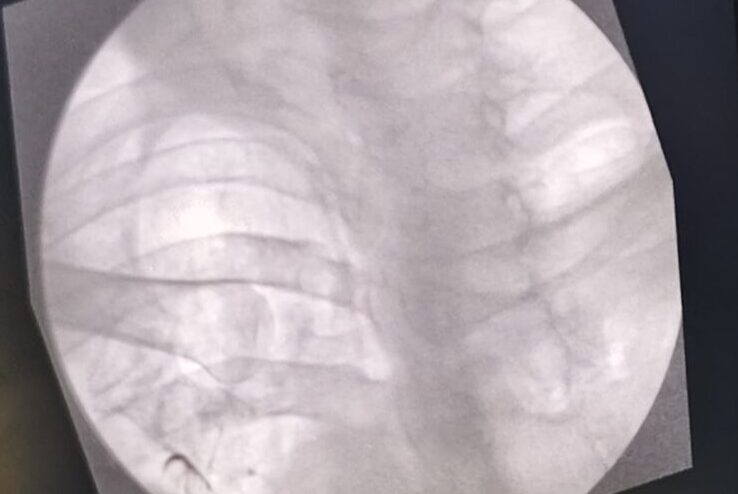

Radiofrequency ablation

- RFA intercostal nerve

- RFA coeliac plexus

- RFA superior hypogastric plexus